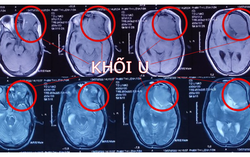

Phòng & chữa bệnh 15:17 22/08/2022Khi đang mang thai 22 tuần, thai phụ được phát hiện tổn thương u não kích thước lớn ở vùng trán trái, khối u xâm lấn vào hốc mắt trái. BV chỉ định phẫu thuật cấp cứu vi phẫu lấy u nhằm cứu sống mẹ và hy vọng giữ được thai nhi.